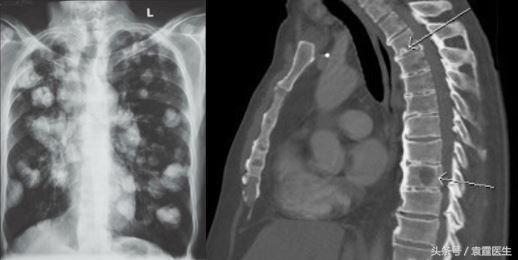

----癌症是如何转移的袁霆骨科学博士上海交通大学硕士研究生导师上海市第六人民医院骨科副主任医师上海市第六人民医院骨肿瘤科副主任医师门诊里常常会有病人或者家属拿着影像学片子让我看,是不是癌症转移了。